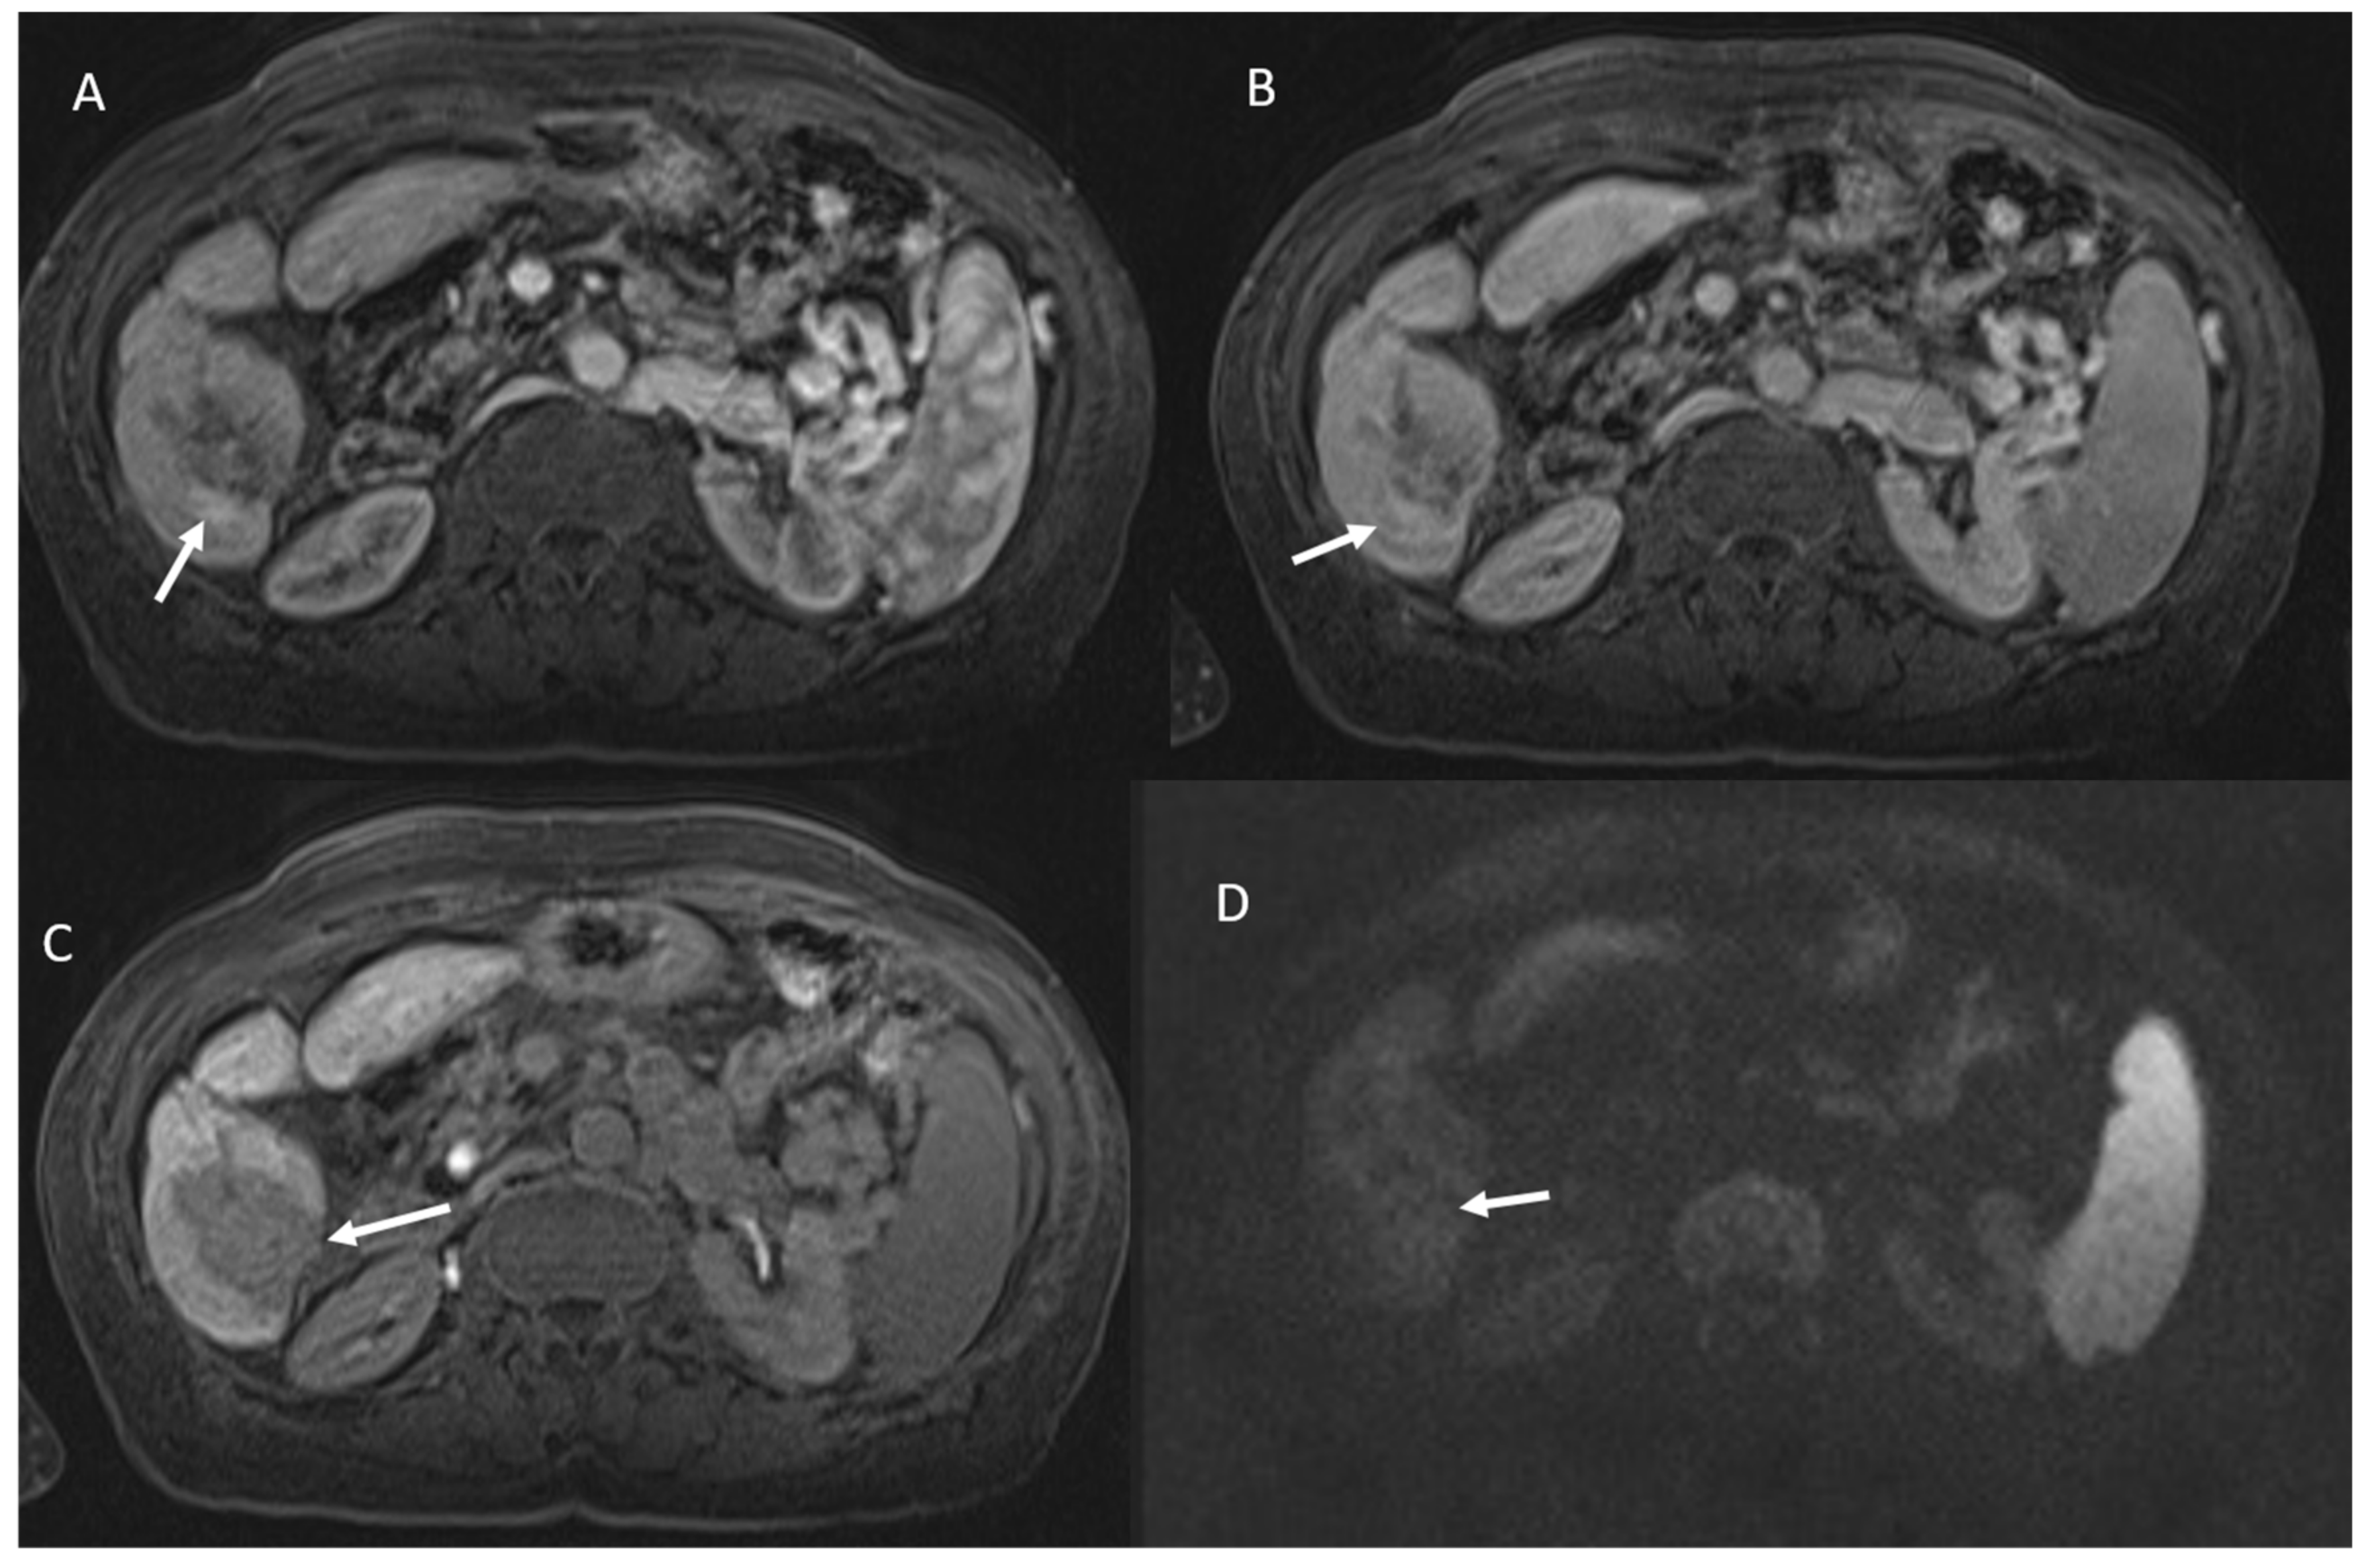

- 23 lesions showed restricted diffusion with hypointense SI in ADC map (Figure 4).

- 84 lesions showed restricted diffusion (Figure 7) with iso-hypointense in ADC map and 29 showed no restricted diffusion.